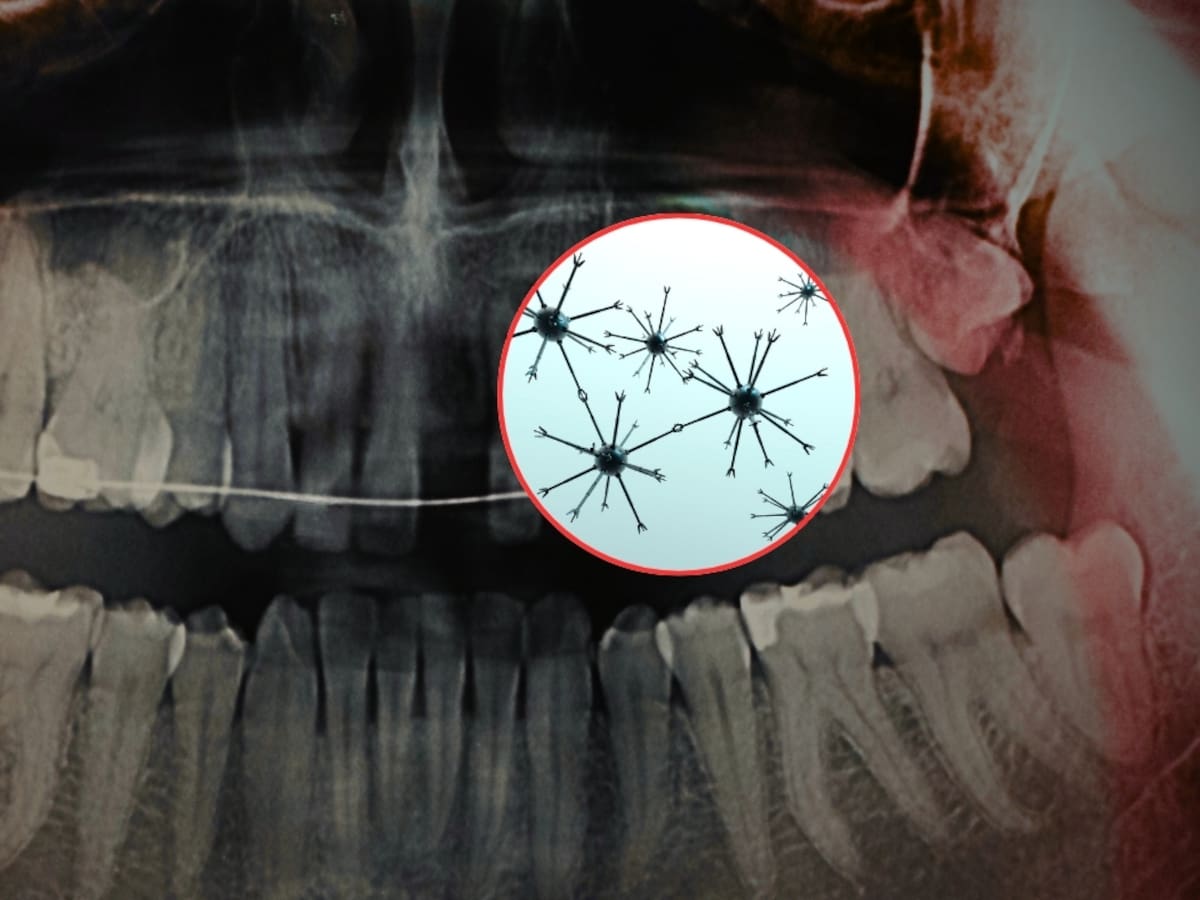

De acuerdo con un estudio publicado en la revista científica Advanced Science y difundido por el Instituto Indio de Ciencias (IISc), en colaboración con la empresa tecnológica Theranautilus, se desarrollaron nanorobots magnéticos llamados Calbots que buscan tratar la sensibilidad dental desde el interior del diente.

Los Calbots son nanorobots magnéticos diseñados para penetrar en los túbulos dentinarios, que son pequeños canales dentro de la dentina que pueden conectar con las terminaciones nerviosas del diente. Cuando estos canales quedan expuestos, se produce la sensibilidad.

Los Calbots miden alrededor de 400 nanómetros y están compuestos por un material biocerámico basado en silicato de calcio. Su funcionamiento se basa en tres pasos principales:

- Guía magnética: se utiliza un campo magnético externo para dirigir los nanorobots hacia los túbulos dentinarios expuestos.

- Penetración profunda: pueden llegar a una profundidad de entre 300 y 500 micrómetros dentro del diente.

- Sellado interno: una vez dentro, se autoensamblan y forman tapones estables similares al cemento, bloqueando los canales que generan la sensibilidad.

Este sellado imita el entorno natural del diente y podría ofrecer un alivio prolongado.